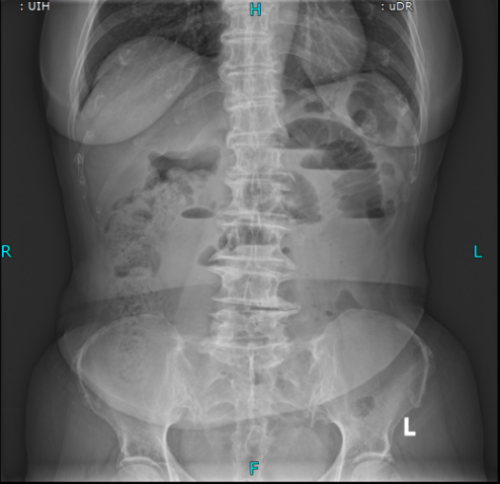

术前立位腹平片

主任医师叶晋生结合病历和CT检查结果,明确诊断:低位小肠梗阻,且王奶奶有两次腹部手术史,肠粘连概率极高,肠管随时可能因过度扩张穿孔,需要先减压再评估。